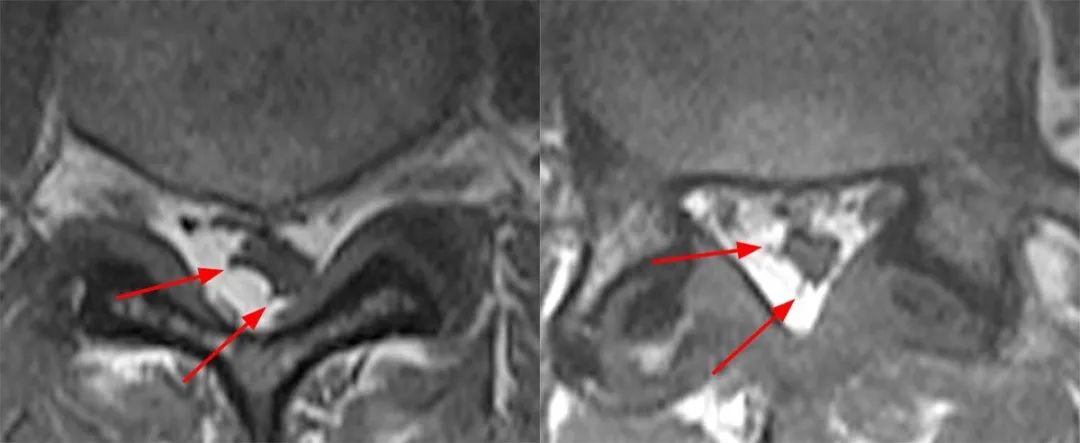

男,32 岁,腰背部疼痛一个月。

发现 L4-5、L5-S1 水平马尾神经位置前移、明显聚拢,马尾神经间脑脊液间隙明显变小。

回过头再看第二个病例,发现椎管内背侧硬膜外脂肪增多,超过椎板前缘,向前推挤马尾神经,使其明显聚拢

SEL 的硬膜外脂肪沉积通常是左右对称的,更罕见的是,它是不对称的。此处,大家会考虑红箭头所示的条样低信号是什么呢?

那么绿箭头所示的其实是硬脊膜椎韧带

同样的,回头看第一个病例也会发现硬脊膜椎韧带,是由于硬膜外脂肪增多而把他显示出来